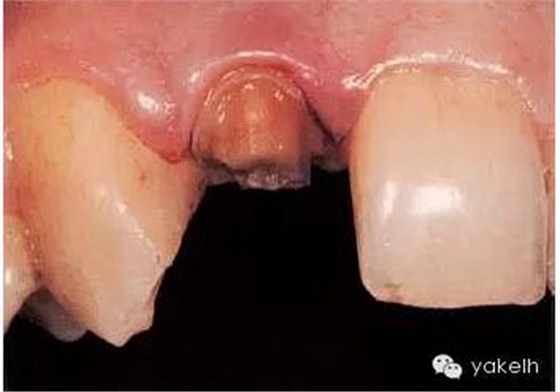

¤¤最終,患者同意12根管再治療后樁核冠修復。臨床上,應在拆除現(xiàn)有修復體、評估冠部剩余牙體量后,方能確定最終治療方案(圖6.3.2)。

圖6.3.2 拆除12現(xiàn)有修復體后剩余的牙體組織。

為什么必須去除現(xiàn)有修復體?

● 評估冠部剩余牙體量,即確定患牙的可修復性。

● 確認牙齒無齲壞,尤其是修復體邊緣有缺損的患牙。

● 髓腔制備時,可最小限度地去除健康牙體組織。原有鑄造冠不能反映牙齒的原始形態(tài)和位置。

● 有助于定位根管口及獲得進入根管的直線通路。

● 根據(jù)剩余牙體量和位置,選擇最合適的方法修復患牙。